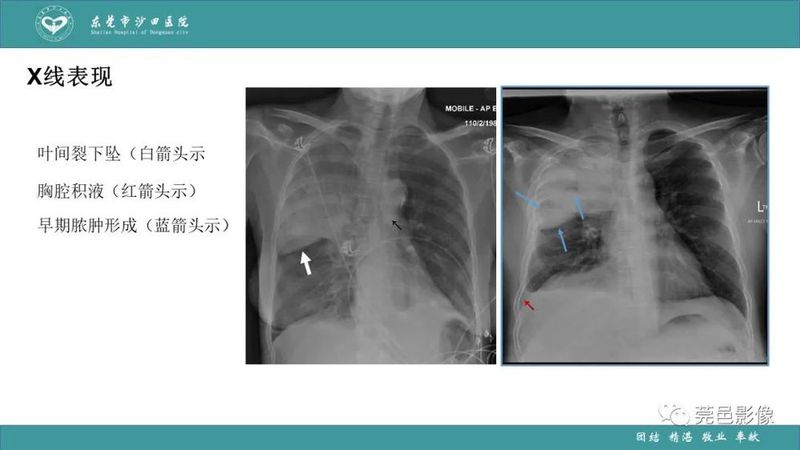

「肺炎克雷伯杆菌肺炎」影像学诊断+鉴别诊断